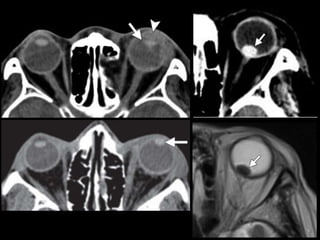

Trauma ocular

• Cámara anterior

– Laceración corneal

– Hifema

• Cristalino

– Luxación

– Catarata traumática

• Segmento posterior

– Desprendimiento de retina

– Desprendimiento coroideo

– Hemorragia vítrea

• Rotura ocular

• Cuerpos extraños

TC

Rotura ocular

• Rotura de la esclera

• Sensibilidad del 56%–68%

– Signos directos:

• Alteración del contorno o volumen (múltiples planos)

• Discontinuidad esclera

– Signos indirectos

• Aumento de profundidad de la cámara anterior

• Aire o cuerpo extraño intraocular

• Mimics

Cuerpos extraños

• Inorgánicos: metal, cristal (sensibilidad 50% en

< 0.5 mm) y plástico. Sin inflamación

• Orgánicos: Madera (densidad similar al aire

pero con forma geométrica) va aumentando

de densidad con el tiempo. RM!

• RM contraindicada en metálicos (más sensible

en orgánicos)

Trauma ocular • Cámaraanterior – Laceración corneal – Hifema • Cristalino – Luxación – Catarata traumática • Segmento posterior – Desprendimiento de retina – Desprendimiento coroideo – Hemorragia vítrea • Rotura ocular • Cuerpos extraños TC

Rotura ocular • Roturade la esclera • Sensibilidad del 56%–68% – Signos directos: • Alteración del contorno o volumen (múltiples planos) • Discontinuidad esclera – Signos indirectos • Aumento de profundidad de la cámara anterior • Aire o cuerpo extraño intraocular • Mimics

Cuerpos extraños • Inorgánicos:metal, cristal (sensibilidad 50% en < 0.5 mm) y plástico. Sin inflamación • Orgánicos: Madera (densidad similar al aire pero con forma geométrica) va aumentando de densidad con el tiempo. RM! • RM contraindicada en metálicos (más sensible en orgánicos)